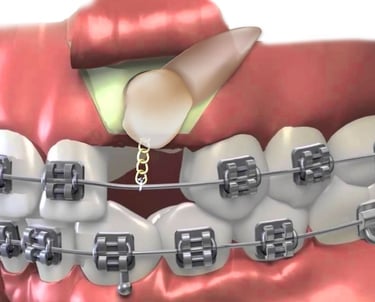

La fenestración en cirugía maxilofacial es un procedimiento quirúrgico que se utiliza para exponer una parte del hueso o un diente que está retenido o impactado dentro de la encía o el hueso. Este procedimiento es común en el tratamiento de dientes que no han erupcionado, como los caninos superiores, o para manejar dientes retenidos.

Fenestración